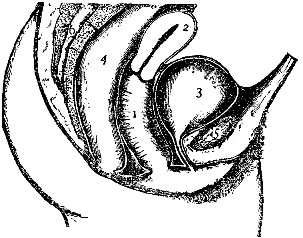

Fig. 2 gives a very good idea of the shape and general structure of this bony framework; while a careful study of Fig. 3 will enable one to form a very correct idea of the relative size and position of the various parts contained in this framework.

The Vagina.—The vagina is a membranous canal extending from the surface of the body to the uterus, or womb. Its posterior wall is about 3½ inches long, and its anterior about 3 inches. A careful study should be made of our illustration, in order that the relation of the vagina and uterus to the rectum behind and the bladder in front may be thoroughly understood; also the angle which is formed by the vagina and the uterus.

Notice should be taken, also, of the opening of the uterus into the upper part of the vagina; as inflammation of the uterus often causes a discharge which passes into the upper part of the vagina and finally out of the body. This gives rise to the belief that the only trouble is in the vagina itself, whereas the real seat of the disease may be high up in the uterus.

The Uterus.—The uterus, or womb, is a hollow organ formed of muscular tissue, and lined with a delicate mucous membrane. The bladder is in front, the rectum behind, and the vagina below.

Three Parts.—Physicians divide this important organ into three parts,—the fundus, body, and neck. The fundus is all the upper rounded portion; the body all that portion between the fundus and the neck; and the neck all the rounded lower part.

The Cavity of the Uterus.—This is divided into the cavity of the body and the cavity of the neck. By consulting our illustration it is seen that these cavities differ greatly in shape; that of the body being triangular, while that of the neck is barrel-shaped.

By referring again to Fig. 4 it will be seen that the cavity of the body has three openings, one on either side at the top going to the Fallopian tubes, and an opening at the bottom passing into the cavity of the neck. A constriction exists between these two cavities; but after childbirth this is largely done away with, and there is not that marked difference which existed formerly.